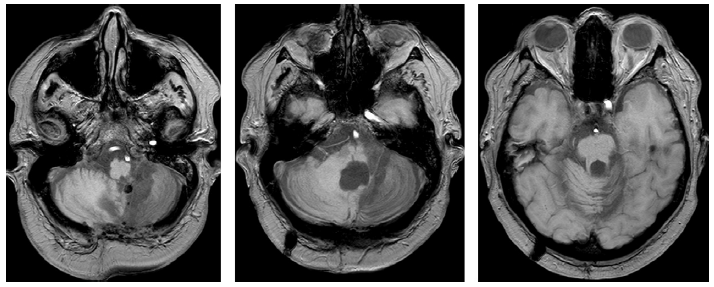

图 2 血管性小脑病变。左:头颅MRI T2加权序列图像可见右侧小脑中脚急性血管病变。中:头颅MRI T2加权序列冠状位图像显示8年后同侧小脑半球萎缩。右:发病9年后随访的头颅MRI FLAIR序列图像显示小脑中胶异常信号和萎缩。